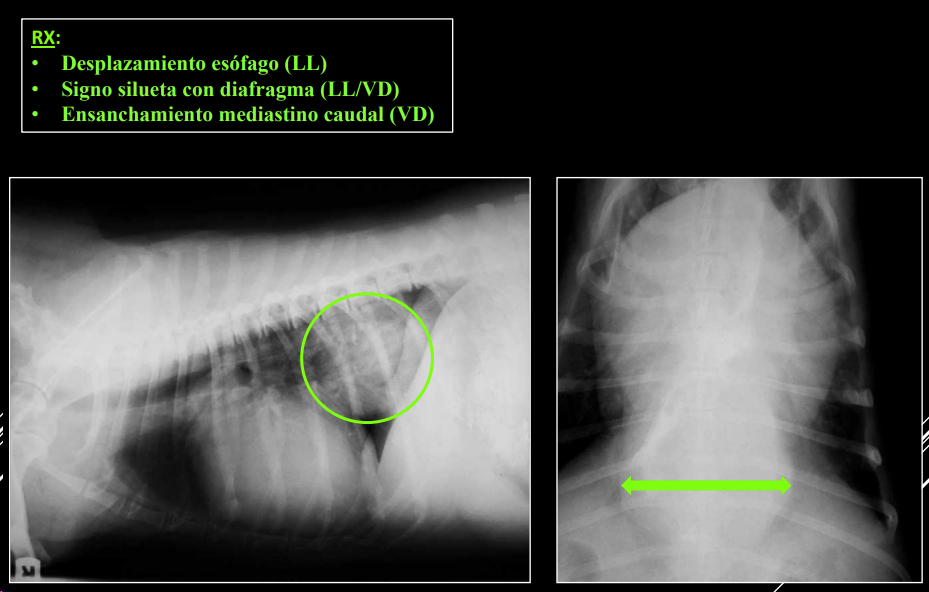

- Alteraciones de posición del mediastino (Desplazamiento mediastino VD)

- Alteraciones de la anchura del mediastino (Derrame mediastinico o masa mediastinica VD)

- Masas mediastínicas (craneodorsales, hilares, caudodorsales, caudoventrales, craneoventrales).

Craneodorsales: alteraciones esofágicas, aneurisma aórtico, hematoma, tumor base cardíaca/neurogénico, absceso, granuloma, lesión vertebral.

Hiliares/Perihiliares: alteraciones esofágicas, tumor base cardiaca, linfoadenopatía traqueobronquial, masa tiroidea ectópica.